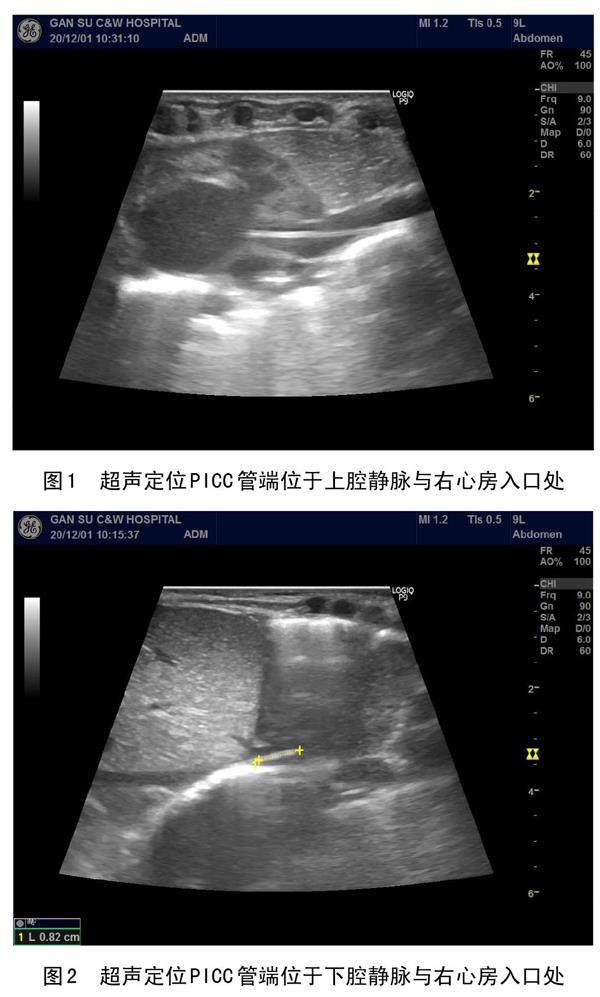

超声引导下在新生儿不同部位留置PICC的应用效果研究

摘要:目的:探讨超声引导下分别在新生儿上肢静脉和下肢静脉留置 PICC 的临床效果差异。方法:选取我院收住630例住院患儿为研究对象,随机分为上肢静脉组和下肢静脉组,记录并分析两组患儿的置管耗时、出血量及一次穿刺成功率等指标。结果:下肢静脉组置管耗时为56.66±37.26,静脉炎发生率5.5%、发热发生率2.7%,明显低于上肢静脉组(65.43±41.61,12.2%,8.6%);下肢静脉组一次穿刺成功率(77.8%)高于上肢静脉组(60.58%),差异有统计学意义(t=2.771,χ2=8.564、9.786、21.72;P<0.05)。(剩余6173字)